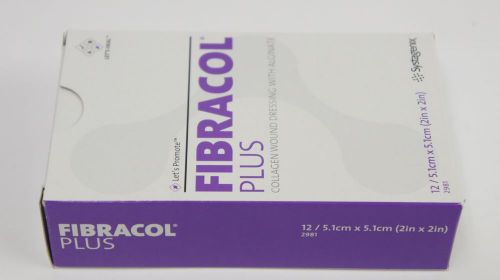

Systagenix 2981 Fibracol Plus Collagen Wound Dressing 2” x 2” ~ BOX OF 12